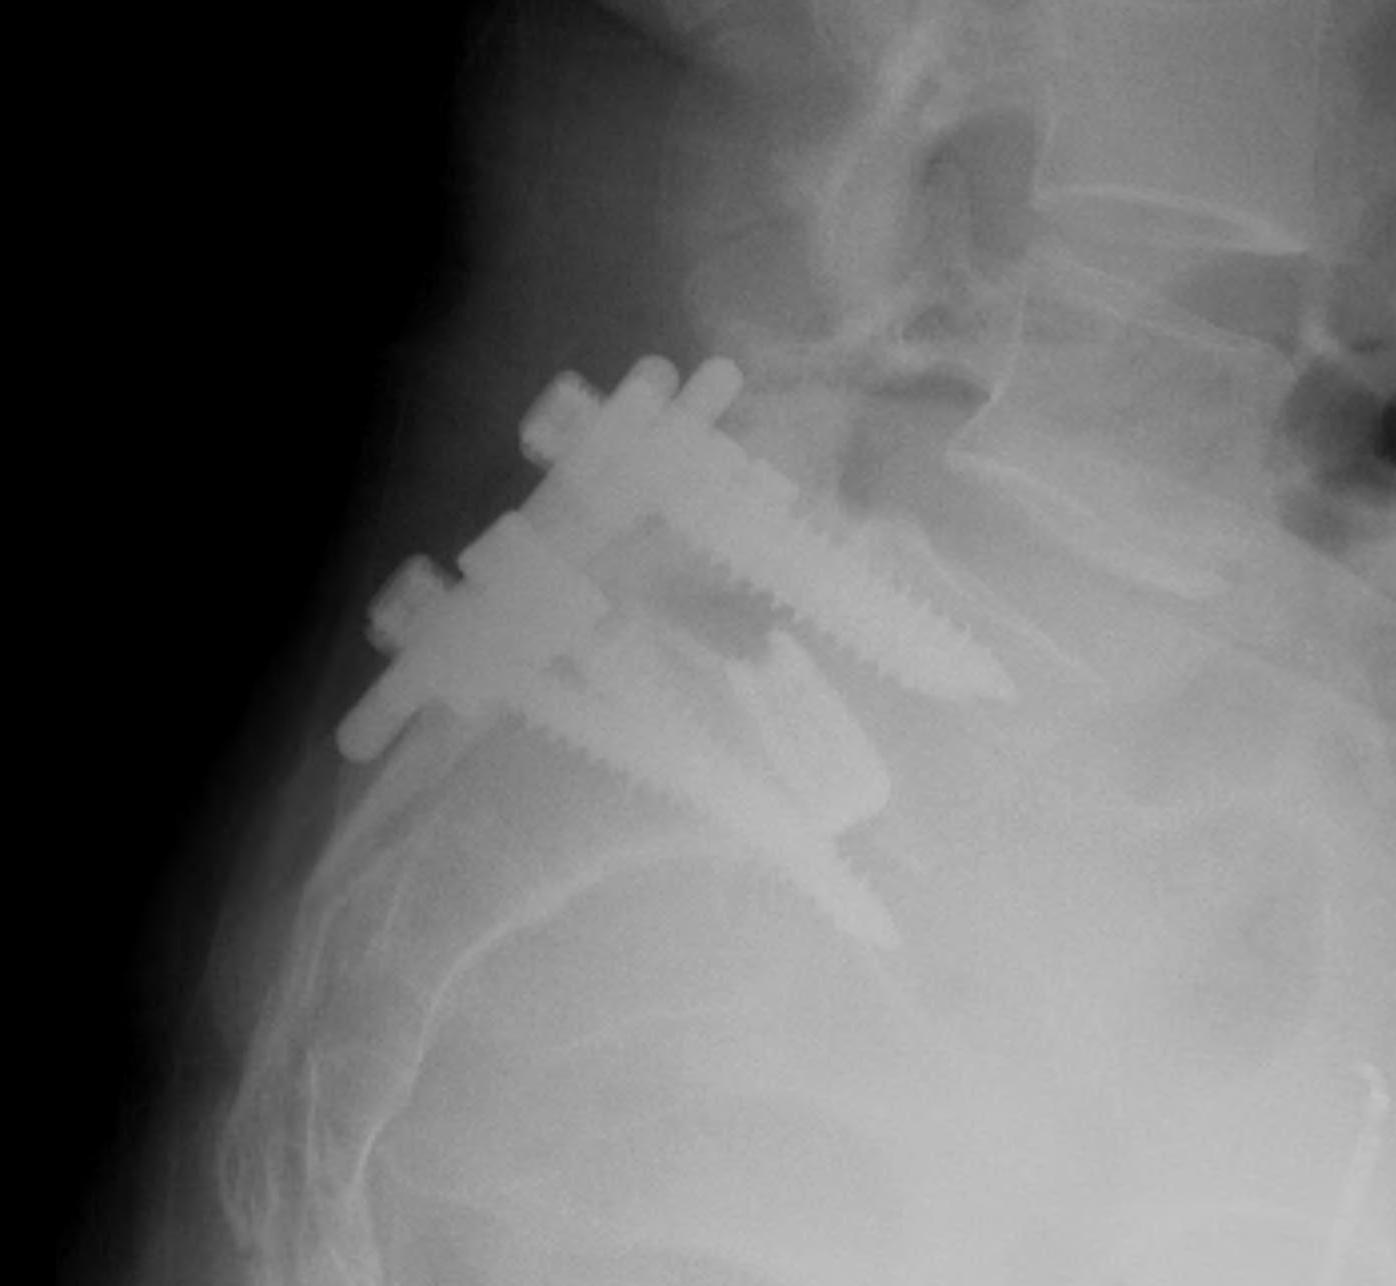

CT scan

Technique

- reverse gantry

Indication

- perform instead of obliques

- oblique x-rays have high radiation dose with little extra information compared with CT